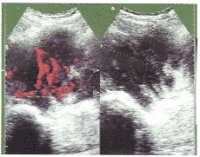

现以上所述的异常症状的话,请去专门医院就诊。横纹肌肉瘤比较早期就容易转移到其他脏器,所以,如果通过画像诊断发现肿瘤的话,要马上住院接受手术。正确的诊断要通过肿瘤病理检查。正确诊断对决定以后的治疗方针是极其重要的。检查项目包括超声波CTMRI。横纹肌肉瘤比较早期就容易转移到其他脏器,所以,如果通过画像诊断发现肿瘤的话,要马上住院接受手术。正确的诊断要通过肿瘤病理检查。正确诊断对决定以后的治疗方针是极其重要的。

影像学检查:一般无典型的放射学特征,通常无钙化现象。肿瘤可侵蚀并破坏邻近骨质,尤以颅骨前臂、手部和足部多见。应用加造影剂的CT和MRI检查,可较好地显示肿瘤的部位、体积、边缘及其与周围组织的关系。静脉肾盂造影可发现膀胱内不规则充盈缺损肾盂积水等。其它的检查方法包括骨扫描(疑有骨转移)和淋巴管造影(疑有淋巴结转移)。

肿瘤好发于眶上部,尤其鼻上象限眼睑处,也可发生在球后或眶内任何部位,约一半位于哐上方者有上睑表现为急性发病,眶缘部肿块可在短期内迅速增大,很快发展为单侧突眼,结膜水肿,上睑下垂,皮肤充血、肿硬,伴发热,可误诊为眶蜂窝织炎。如肿瘤侵及视神经眼外肌,则视力丧失眼球运动障碍。如不及时治疗,肿瘤可蔓延整个眼眶,累及鼻窦,甚至进入颅内。立即进行CT、MRI和B超等影像检查,能明确肿瘤的部位和范围,CT检查在儿童如显示眶骨破坏则有助于确诊。如临床诊断不明确,可作活检病理诊断。此外,应体检耳前、颈淋巴结有否局部转移。